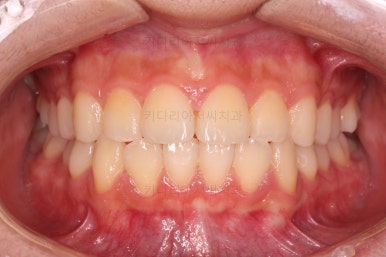

초진 시 다른 부위들 사진입니다.

약간의 주걱턱 느낌에 약간의 돌출감, 전반적인 치열의 가지런한 느낌은 나쁘지 않았지만 약간의 불량한 교합상태였어요.

다른 부분은 크게 바꾸지 말고 약간의 교합조절과 어금니 치료에 초점을 맞춰서 교정치료 계획을 잡았습니다.

전후사진을 비교해볼게요.

약간의 주걱턱, 돌출입은 고칠 의사가 없어서 그대로 유지하였고 주걱턱 패턴으로 인한 부정교합 부분을 개선했으며 무엇보다 중요한 것은 쓰러져서 많이 썩어있던 치아를 자칫 치료 못할 뻔 했는데 교정치료와 병행하여 훌륭하게 치료하여 살려 썼다는 점이었어요.